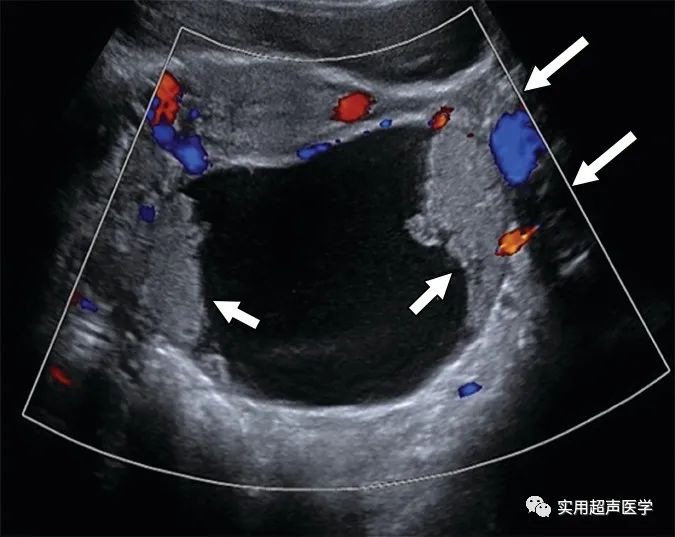

68岁女性腹胀,左卵巢交界性浆液性囊腺瘤。彩色多普勒超声图像显示多房囊肿,内壁和分隔不规则(箭头),无实性成分,符合卵巢-附件报告和数据系统 (O-RADS) 4 类病变。当多房囊肿的内壁或分隔不规则时,代表内部血管和大小的颜色评分 (CS) 无助于 O-RADS 风险评估。